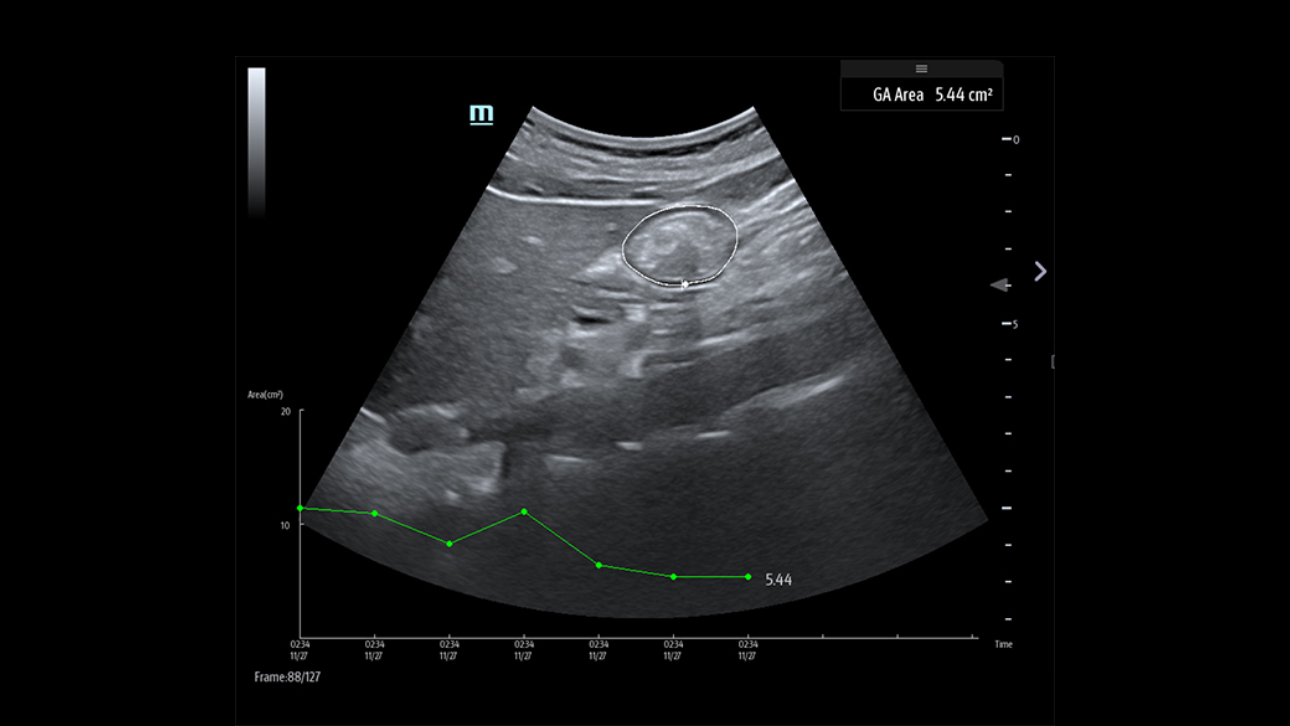

X-Pilot: Clinical Application-Oriented Workflow

Based on the professional society guidelines for point of care ultrasound, the X-Pilot suite integrates historical diagnostic images and multi-organ data into a concise and precise view of the patient status to support rapid clinical decisions at the bedside.